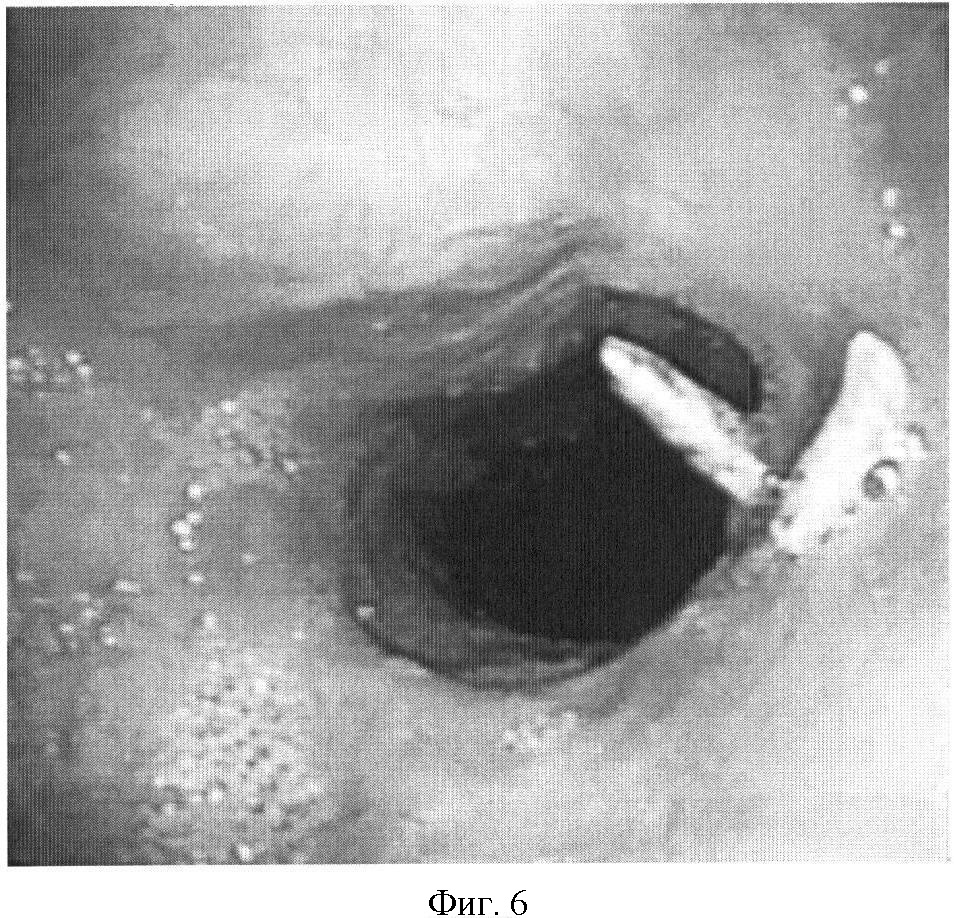

На фиг.1 представлена рентгенограмма пищевода с контрастным веществом: определяется контрастирование трахеопищеводного свища. На фиг.2 представлена эндоскопическая картина просвета пищевода: устье трахеопищеводного свища указано стрелкой. На фиг.3 представлена эндоскопическая картина просвета пищевода: предварительно в устье трахеопищеводного свища, открывающегося в просвете трахеи, было ведено 0,8 мл красящего вещества (метиленовой сини), после этого в просвете пищевода определяется прокрашивание устья трахеопищеводного свища (указано стрелкой). На фиг.4 – пломбирование устья трахеопищеводного свища тахокомбом, предварительно устье свища было последовательно подвергнуто электрокоагуляции и химиокоагуляции (96% этиловый спирт). На фиг.5 – клиппирование запломбированного устья свища. На фиг.6 – контрольная эзофагоскопия, выполненная через 3 месяца после операции: в просвете пищевода в области устья трахеопищеводного свища определяются две скрепки. На фиг.7 – контрольная рентгенограмма после эндоскопического лечения (через 3 месяца): в области трахеопищеводного свища определяется незначительный дефект наполнения (указан стрелкой), трахеопищеводный свищ не контрастируется.